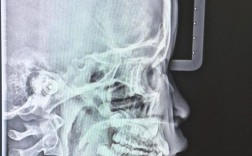

• 正畸诊断中X线检查为何不可或缺?不同类型X线片如何辅助分析牙齿、颌骨及咬合关系的异常?

正畸诊断中X线检查为何不可或缺?不同类型X线片如何辅助分析牙齿、颌骨及咬合关系的异常?

正畸诊断中常用X线检查类型及其核心应用全景片(曲面断层片-PanoramicRadiograph,OPG/Panorex)成像原理:患者站立不动,X线球管和胶片/探测器围绕患者头部做360°或270°旋转,获得一张包含上下颌骨、牙...